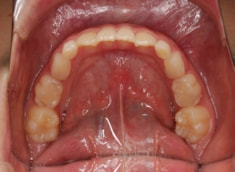

治療後(1年7ヶ月後)

フェイスマスクによる上顎の前方牽引の効果が認めらます。

治療前後の重ね合わせから、フェイスマスクの効果が認められます。

フェイスマスクの効果が得られております。